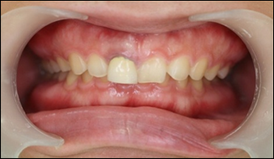

他院では歯を抜いて3か月程して、骨が回復した後にインプラントを入れる為、治療期間が半年かかると言われました。しかし当院では抜歯即時埋入という、歯を抜いて当日にインプラントを入れる治療法を行ったため3か月で治療を終える事が出来ました。

また抜歯即時埋入と同時に抜歯即時加重という、インプラントを埋入した当日から物を噛めるような歯を入れる治療法を併用したため、治療期間中、前歯部でも審美性を失わずに治療をすることができました。

完成後の口腔内写真